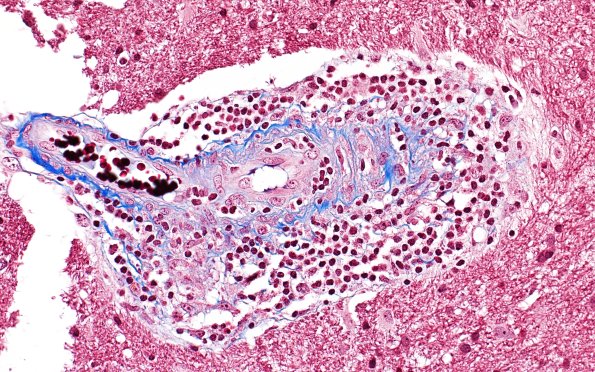

Vasculitis - PACNS

17D1 Vasculitis (Case 17) TRI 40X 1

This trichrome stain shows pockets of inflammatory cells. (Trichrome)